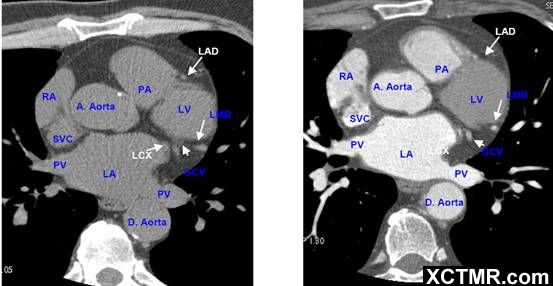

常用英文名称及缩写 LA - Left Atrium 左心房 RA - Right Atrium 右心房 LV - Left Ventricle 左心室 RV - Right Ventricle 右心室 Mitral Valve 二尖瓣 A. Aorta-Ascending Aorta 升主动脉 D. Aorta-Descending Aorta 降主动脉 SVC – Superior Vena Cava 上腔静脉 IVC – Inferior Vena Cava 下腔静脉 PA - Pulmonary Artery 肺动脉 PV - Pulmonary Vein 肺静脉 LMA - Left Main Artery 冠状动脉左主干 LAD - Left Anterior Descending Artery 左前降支 LCX - Left Circumflex Artery 左回旋支 LMB - Left Obtuse Marginal Branch 左边缘支(钝缘支) RCA - Right Coronary Artery 右冠状动脉 PDA - Posterior Descending Artery 后降支 Conus Branch 右动脉圆锥支 LAA – Left Atrial Appendage 左心耳 RAA – Right Atrial Appendage 右心耳 CS - Coronary Sinus 冠状窦 MCV – Middle Cardiac Vein 心中静脉 GCV –Great Cardiac Vein 心大静脉 PIVV – Posterior Intraventricular Vein 后室间静脉(心中静脉) PLVV – Posterior Left Ventricular Vein 左室后静脉 PLV – Posterior Lateral Vein 左室后侧静脉(边缘静脉) | |